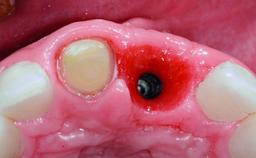

Replacement of a Failing Restored Upper Right Central Incisor, Ridge Preservation and Early Placement of an RC Bone Level Implant

A 23-year-old female, healthy and non-smoking patient had had tooth 11 temporarily restored following a trauma in adolescence. As the patient’s growth had since come to an end and the crown had fractured, she requested an implant-supported restoration of tooth 11. Moreover, the contralateral tooth 21 presented an old composite restoration at the mesial incisal edge. The periodontal tissues were healthy with periodontal probing depth values below 3 mm, but some inflammation was observed around the semi-submerged root of tooth 11.